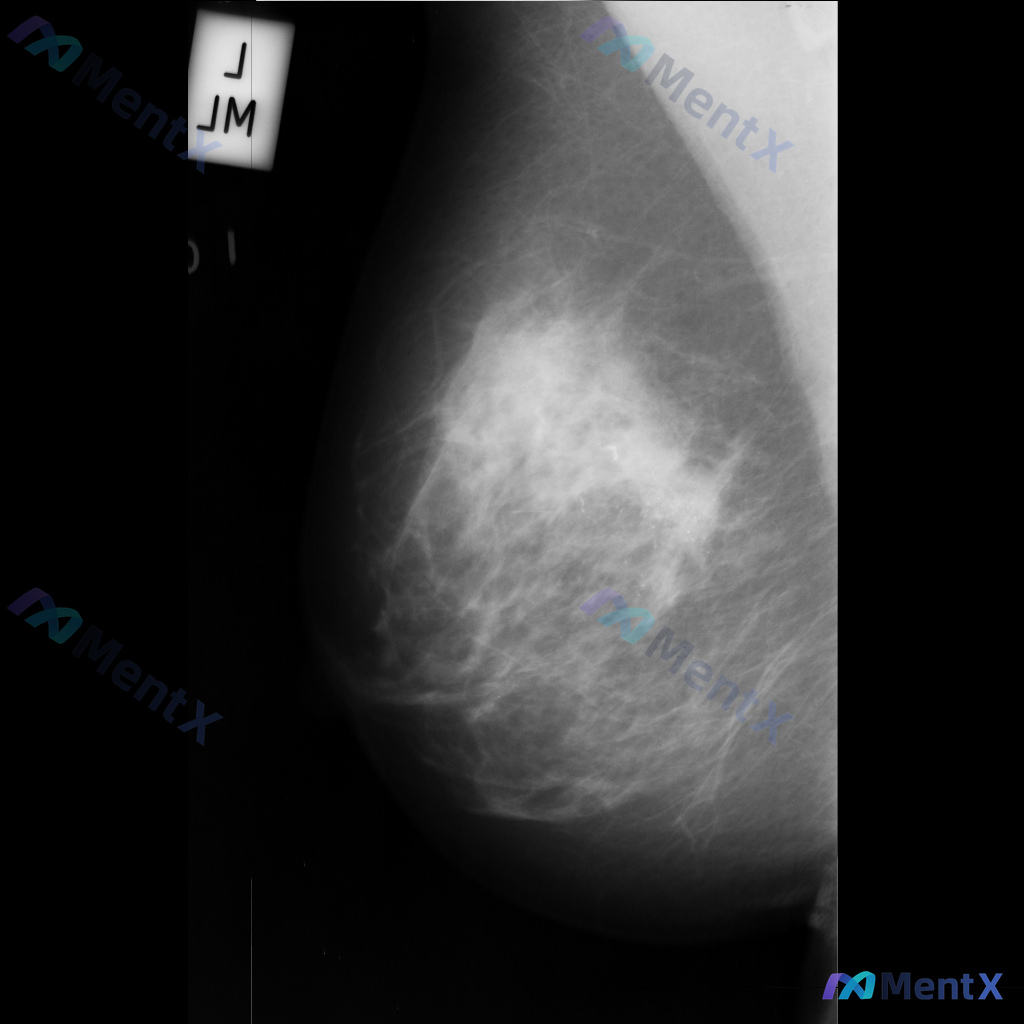

整理到一份乳腺钼靶的影像描述资料,大家一起看看这种情况会先往哪个方向考虑? 影像为左侧乳腺内外斜位(MLO)钼靶图像,主要发现: - 存在一处边界模糊、形态不规则的致密影 - 内部密度不均,可见散在的微小点状高密度影(可疑钙化) - 致密影与周围腺体组织界限不清,可能伴有结构扭曲 单看这组影像描述,...